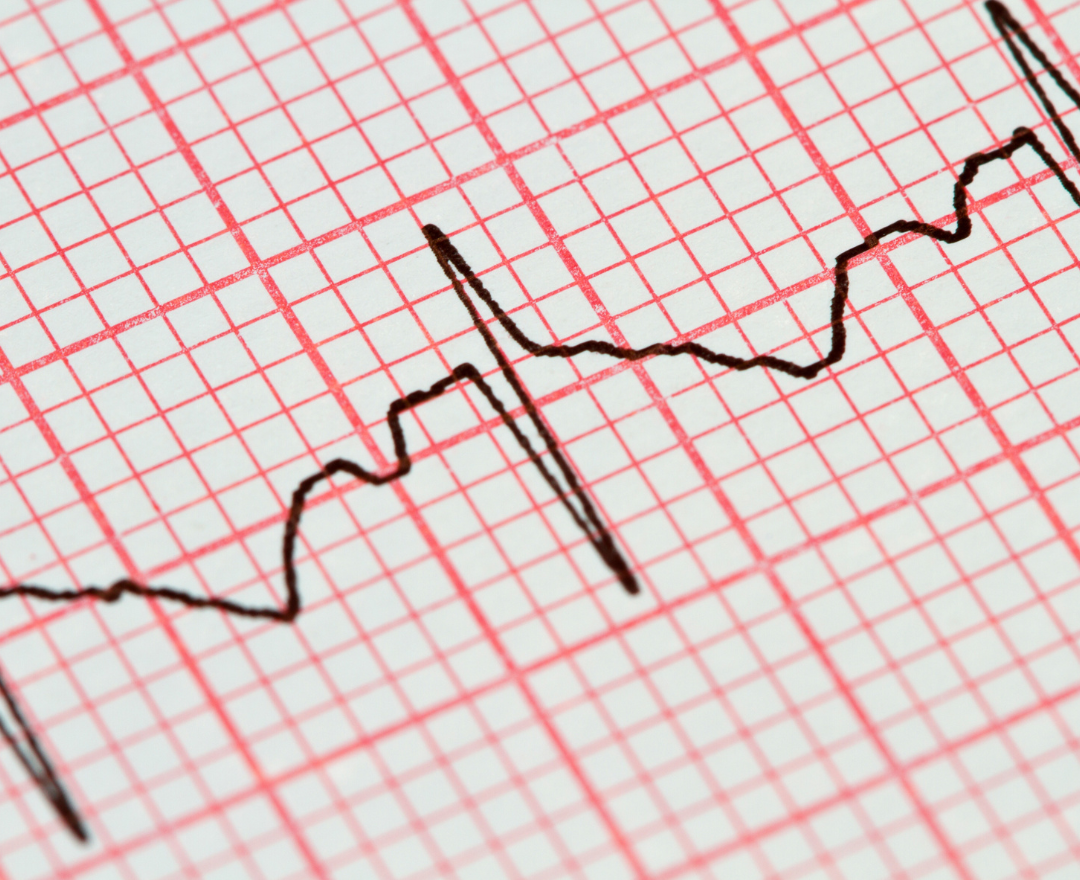

O eletrocardiograma, ou ECG, é um dos exames cardíacos mais realizados no mundo.